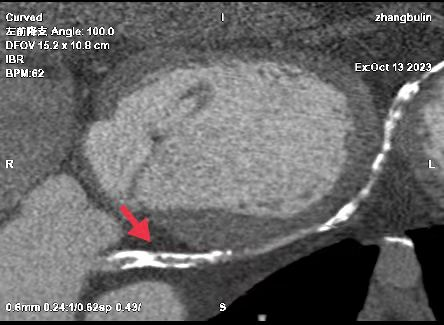

01、**男士,61岁

于2023年11月9日在邯郸仁泰东区体检,冠脉CTA检查提示:冠脉分布呈右优势型。左冠状动脉主干起自主动脉左窦后上方,随即分支为左前降支及回旋支。左、右冠、回旋支及部分分支多发大小不等钙化斑块,局部管腔均呈不同程度狭窄,前降支近、中段、回旋支中段、右冠中段局部管腔均达重度狭窄。首次回访2023年11月10日,通知客户到三甲医院进一步检查和治疗。2023年11月24日跟踪回访,客户已在北京某三甲医院完成支架手术。